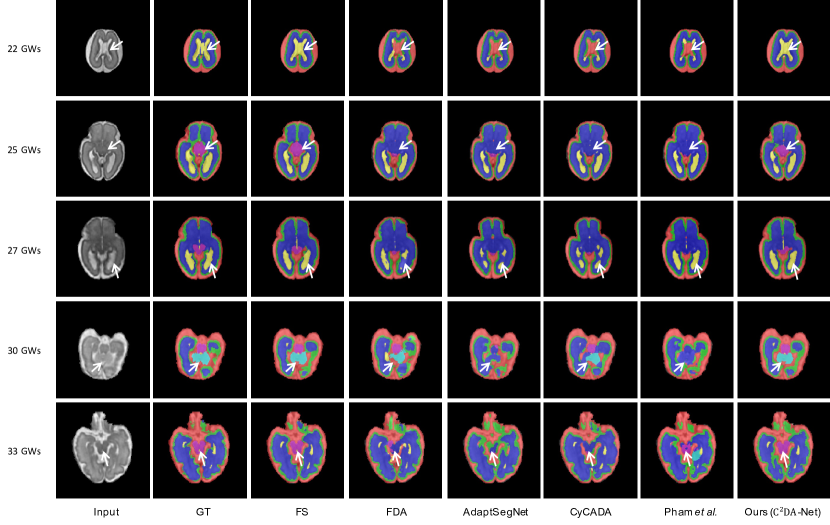

Refer to caption

Figure 5: Qualitative comparison of different methods for subjects at 22 GWs, 25 GWs, 27 GWs, 30 GWs, and 33 GWs, respectively. Typical results are shown row-by-row. The red, green, deep blue, yellow, shallow blue and purple stand for CSF, GM, WM, ventricles, cerebellum, and brainstem, respectively.

Figure 6: Qualitative results of different methods in three orthogonal views from a single subject. Typical examples are shown row-by-row.

Next, we compare our method with state-of-the-art UDA methods to validate its effectiveness. The quantitative and qualitative comparisons are presented in Table 1, Fig. 5 and Fig. 6. Our method achieves the best performance in the segmentation of six tissues and multi-view images, demonstrating the advantages of the proposed method in domain adaptation based segmentation. An interesting observation is that the three state-of-the-art UDA methods provide relatively small performance improvement, which can be explained from two aspects. First, the limited intensity contrast among different tissues can pose a challenge for methods that align different domains in image space, which can result in limited improvement in low-intensity contrast areas. Second, the target and source domain data are with the same imaging modality (i.e., T2-weighted MR images), making it difficult to extract domain-invariant features and avoid falling into a local optimum during adaptation. The low Dice accuracy of ANTs suggests that the registration process is not precise enough for achieving accurate segmentation. To demonstrate the advantage of our method, we provide five qualitative segmentation samples from different GWs in Fig. 5. It can be observed that our method matches the ground truth well, especially at the boundaries between brain tissues with limited intensity contrast.